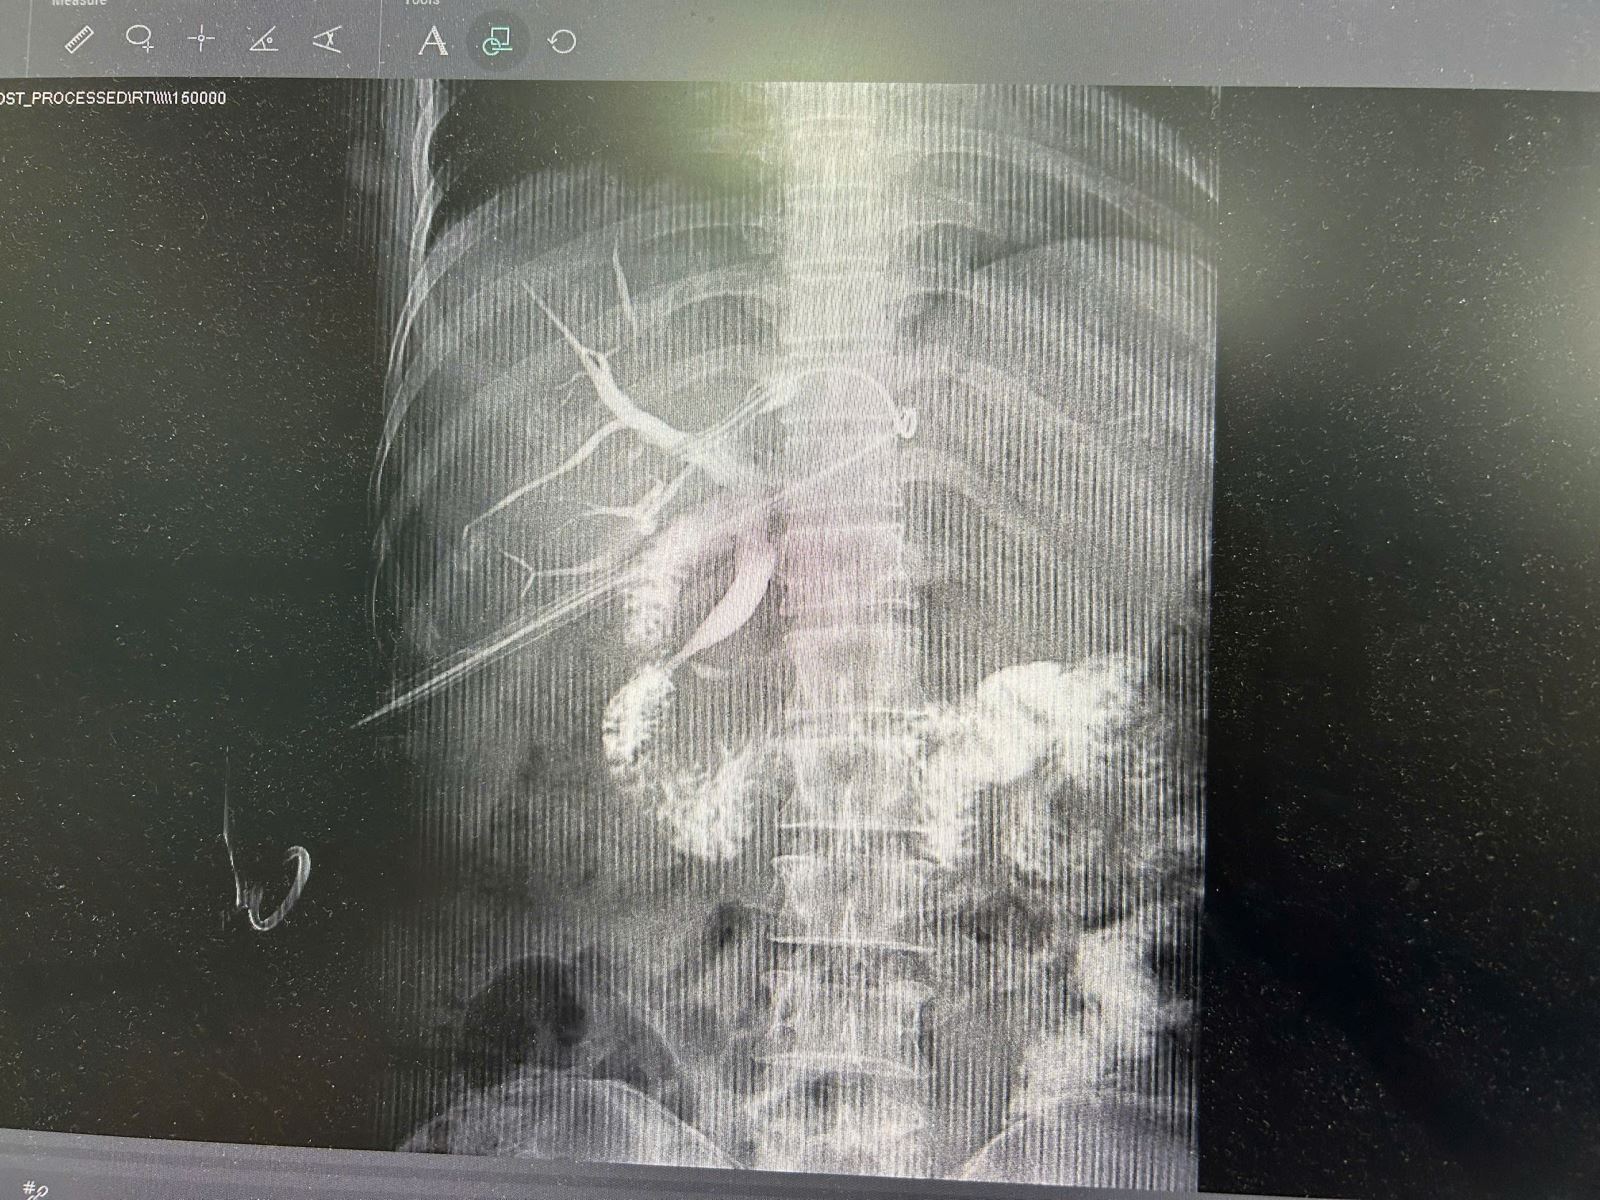

Hình ảnh ống mật đã được làm sạch sỏi sau phẫu thuật trên bệnh nhân N.T.L 45 tuổi

Ca phẫu thuật kéo dài khoảng 2 giờ đồng hồ, khi kết thúc người bệnh được kiểm tra lại bằng Xquang, siêu âm đường mật đảm bảo không còn sỏi sót lại.

Dưới hướng dẫn của máy siêu âm và hệ thống chụp mạch số hóa xóa nền DSA, các bác sĩ Khoa Ngoại tổng hợp và Chẩn đoán hình ảnh giàu kinh nghiệm tiến hành phẫu thuật, nong đường mật để đưa dụng cụ vào kiểm tra toàn bộ hệ thống đường mật trong gan và tán nhỏ sỏi, hút ra ngoài, sau đó bơm rửa lấy hết cặn sỏi cho người bệnh.

Với kĩ thuật tán sỏi đường mật qua da, Bác sĩ sẽ tiếp cận bằng 1 đường xuyên qua da từ 3-5mm vào đường mật trong gan dưới hướng dẫn của máy chụp mạch số hóa xóa nền DSA, máy siêu âm trong mổ và camera nội soi. Sau khi tạo được đường hầm nhỏ vào đường mật trong gan, một bộ nong rộng đưa máy tán sỏi laser công suất lớn sẽ kiểm tra toàn bộ hệ thống đường mật trong gan (ống gan phải, ống gan trái, toàn bộ ống mật chủ). Các vị trí phát hiện có sỏi sẽ được tán nhỏ, hút ra ngoài và bơm rửa lấy hết cặn sỏi. Kết thúc ca tán sỏi, người bệnh được kiểm tra lại bằng Xquang và siêu âm đường mật, đảm bảo không còn sót sỏi.